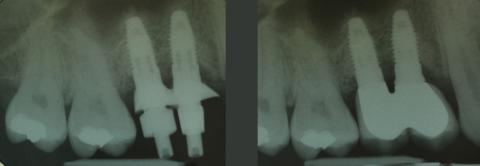

Aufgrund lehrgangsbedingter Abwesenheit des Patienten konnte erst im März 2007 die Implantation Regio 14 und 15 geplant werden. Aufgrund der präoperativen Diagnostik mit Panoramaschichtaufnahme war bei einer Restknochenhöhe über der Kieferhöhle von jeweils ca. 5 mm eine Augmentation im Sinne eines Sinusliftes zu erwarten. Der Patient wurde darüber aufgeklärt, dass dies möglicherweise nicht mittels eines geringen invasiven Vorgehens über den Bohrschacht (interner Sinuslift) realisierbar wäre, sondern bedingt durch die grenzwertige Restknochenhöhe und -breite eine laterale Fensterung der Kieferhöhle (externer Sinuslift) möglicherweise nötig wäre. Die Insertion von zwei Nobel Replace Select Tapered Implantaten 4,3 x 10 mit 35 Ncm gelang Ende März 2007 doch mit Anheben des Kieferhöhlenbodens über den Bohrstollen in Osteotomtechnik nach Summers (interner Sinuslift) und Einbringen von bovinem Knochenmaterial in porciner Matrix (BioOss Collagen, Firma Geistlich Biomaterials). Ein crestobukkaler Defekt, der sich innerhalb der Kontur des Alveolarfortsatzes befand, konnte mit Knochenspänen aus dem Bereich der crista zygomaticoalveolaris aufgefüllt und so insgesamt auf die erwartete komplexere Augmentation verzichtet werden. Das Augmentat wurde mit einer resorbierbaren porcinen Kollagenmembran (BioGide, Firma Geistlich Biomaterials) abgedeckt. Nach einer Woche wurden die Nähte entfernt, der Bereich verblieb ohne provisorische Versorgung.

Im vorliegenden Fall wurden die verblockten definitiven Kronen aus verblendetem Zirkondioxyd erst im April 2008 angefertigt und eingegliedert, da der Patient an Lehrgängen teilnehmen musste. Die Abformpfosten wurden dabei individualisiert, um das mit dem Provisorium ausgeformte Emergenzprofil in die Abformung zu übertragen. Die Zementierung der Kronen auf den Titanaufbauten erfolgte mittels Glasionomerzement.

Die Versorgung ist mittlerweile über 14 Jahre bei stabilen Verhältnissen in situ. 2020 wurde sie einmal andernorts rezementiert. Der Patient befindet sich weiter im halbjährlichen Recall.